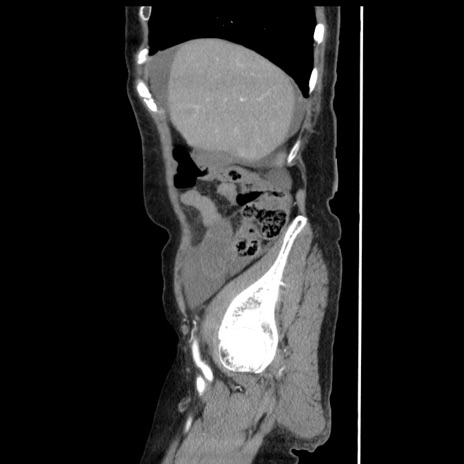

冠状断像